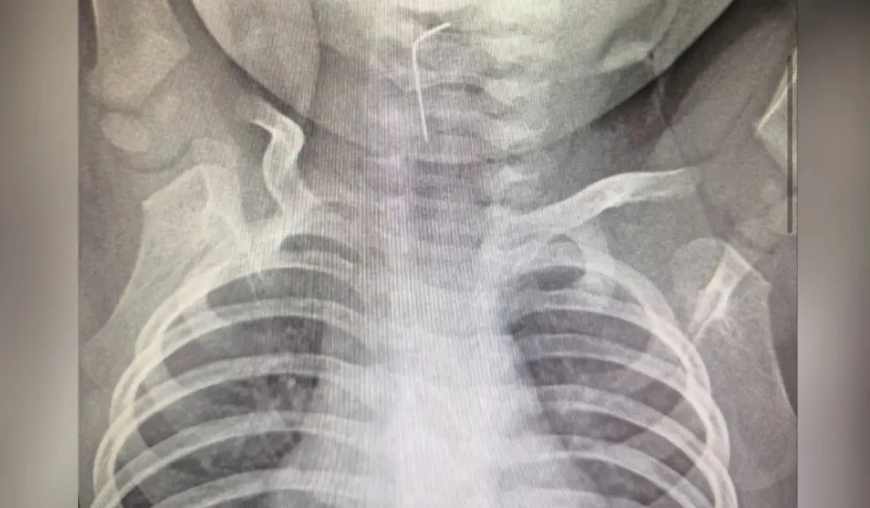

Фото: Түркістан облыстық әкімдігі

Түркістан облыстық балалар ауруханасына тоғыз айлық бала шұғыл жеткізілді. Себебі сәби кездейсоқ ине жұтып қойған, деп хабарлайды Sadaq.kz.

Дәрігерлер рентгенологиялық тексеру жүргізіп, эндоскопиялық әдіс қолданды. Мамандар бөгде заттың нақты орналасқан жерін анықтап, өңешке қадалған инені сәтті алып шықты.